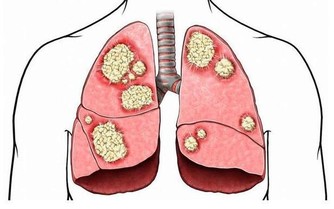

毒素不清,會累積成癌  在大腸癌的發生部位和發生機率中,直腸和乙狀結腸得癌症的機率最高,幾乎有百分之七十的腸癌都集中從肛門上來六十公分的這一段,因為這裡是宿便最容易囤積的地方,毒素都累積在這裡,這段腸子就像家裡的垃圾桶,等到垃圾積滿了才會去倒。咖啡灌腸最主要就是針對這一段腸道進行清腸排毒。

腸癌目前高居國人癌症發生人數的第一名,是有跡可循的,證明現代人飲食中的毒素真的太嚴重,加上排泄不良,宿便的毒素都累積在大腸內。